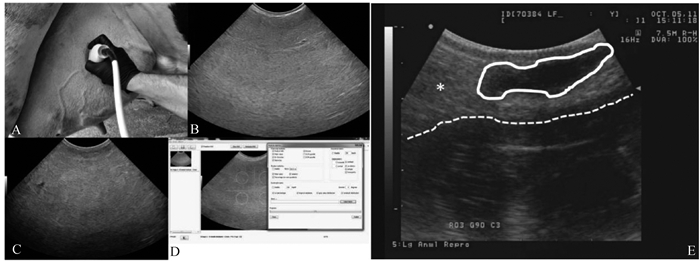

Ultrasound detection images[75, 89] A. Ultrasound detection of mammary parenchyma; B. Ultrasound image of the right posterior mammary gland of a cow on day 75 of lactation; C. Ultrasound image of the right posterior mammary gland of a cow on day 7 of dry milking; D. Echotexture analysis of the mammary ultrasound image; E. Ultrasound image of mammary gland of calf at 8 weeks of age. White circle. Mammary parenchyma (hypoechoic); asterisks. Mammary fat pads (hyperechoic); dotted line. Marking of the body wall"